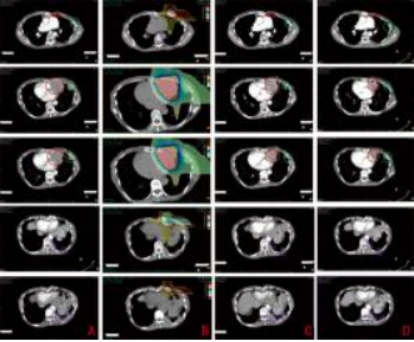

Figure 2 Beam direction and composite dose distribution (one left lateral field + one vertical field)

A: Before carbon ion therapy (March 24, 2020); B: Dose distribution map (1%–110%); C: After carbon ion therapy (April 10, 2020); D: One year after carbon ion therapy (April 19, 2021); Red - Target dose irradiation area; Green - Low-dose irradiation area; Purple - Non-irradiated area

Figure 3 Imaging of chest lesions before and after treatment

Case Report: A 43-year-old female patient with no significant past medical history, denies smoking or chronic lung disease. The patient presented to Wuwei Cancer Hospital in February 2009 with complaints of palpitations and shortness of breath for 4 months, 10 years following postoperative radiotherapy for thymic carcinoma. Chest CT revealed a mass in the anterior superior mediastinum, suggesting a thymic tumor with invasion of the pericardium and left lung (Figure 1A). On February 16, 2009, the patient underwent "extensive resection of thymic tumor + partial resection of the left upper lobe of the lung, phrenic nerve, and pericardium." Postoperative pathology showed: (anterior superior mediastinum) thymic non-keratinizing squamous cell carcinoma. The tumor invaded the pericardium and lung, with no involvement of major blood vessels or lymph nodes. Pathological diagnosis: Masaoka stage IIIa, type C: thymic carcinoma. Postoperative chest CT indicated: postoperative thymic carcinoma, triangular effusion under the left sternum and effusion in the anterior pericardial space, extensive thickening and adhesion of the left pleura with a small amount of pleural effusion, local bone defect after sternal surgery, and soft tissue swelling (Figure 1B). Postoperative diagnosis: pT3N0M0 stage IIIa, based on the 8th edition of the American Joint Committee on Cancer (AJCC) staging. The patient received postoperative intensity-modulated radiotherapy (IMRT) 35 days after surgery, with a dose of 50 Gy delivered in 25 fractions, targeting the original tumor bed and the upper mediastinum. Thereafter, the patient received no further treatment and underwent regular chest CT follow-ups. In December 2019, the patient again experienced palpitations and shortness of breath. Chest CT revealed multiple nodules in the left pleura, diaphragmatic crura, and peritoneum, with the largest lesion (6.3 cm × 5.2 cm) located near the pericardium in the left pleura, as well as multiple small lymph nodes in the left neck root, mediastinum, and retroperitoneum, suggesting recurrence and metastasis of thymic carcinoma. The clinical diagnosis was rcT2N2M1a stage IVa. After multidisciplinary team (MDT) consultation, considering the patient’s long disease-free survival after the previous surgery and radiotherapy, and the tumor’s indolent biological behavior, palliative carbon ion radiotherapy was administered to the largest tumor near the left pericardium, which was compressing and invading the heart, to alleviate the patient’s symptoms of palpitations and shortness of breath. Carbon ion therapy was chosen due to its unique biological and physical advantages. The biological characteristics of carbon ions include higher linear energy transfer (LET) and greater relative biological effectiveness (RBE), as well as a low oxygen enhancement ratio (OER) that is unaffected by tumor hypoxia, thereby improving local tumor control. [1]The physical characteristics of carbon ions, such as the Bragg peak and minimal lateral scattering, allow for more precise radiation dose distribution1. Thus, while delivering a high dose to the tumor, the radiation dose to the heart and lungs can be minimized, protecting critical organs. Treatment plan: The patient was placed in the prone position with hands crossed above the head, left hand on top, and a pillow under the forehead. Dual immobilization was achieved using a large vacuum cushion and thermoplastic film. CT scans were performed with a slice thickness of 3 mm, including plain, contrast-enhanced, and 4D sequences. The CT images were transferred to the "rtStation" planning system for target delineation. Target delineation: The gross tumor volume (GTV) included the largest tumor visible on imaging near the left pericardium; the clinical target volume (CTV) was defined as GTV with a 5 mm margin; the planning target volume (PTV) was defined as CTV with a 5 mm margin. Adjustments were made to protect critical organs, with a 1 cm safety margin left near the left ventricle. Treatment planning: Carbon ion treatment planning was performed using the Ci-plan software. The treatment plan required that 90% of the PTV receive the prescribed dose. One left lateral field and one vertical field were used, with a total dose of 60 GyE delivered to the lesion (Figure 2). The single dose was 4 GyE, administered once daily, 5 times per week (Monday to Friday), for a total of 12 fractions over 3 weeks. The dose of carbon ions was expressed in photon equivalent dose (GyE), where GyE is defined as the physical dose multiplied by the RBE of carbon ions, with the with a relative biological effectiveness (RBE) of carbon ions typically set at 3.0[2]. During and after treatment, the patient received no other therapies. After treatment, the patient’s symptoms of palpitations and shortness of breath were relieved. During treatment, only mild skin pigmentation was observed at the treatment site, classified as grade 1 skin reaction according to the Radiation Therapy Oncology Group (RTOG) acute radiation injury grading criteria, and grade 1 radiation dermatitis according to the Common Terminology Criteria for Adverse Events (CTCAE) version 5.0. The skin reaction resolved completely 2 months after radiotherapy. Chest CT performed on the day of treatment completion showed not only shrinkage of the largest lesion at the irradiated site (left pericardium), but also varying degrees of shrinkage in metastatic lesions at other sites that received low-dose or no irradiation (left chest wall and left diaphragmatic crus), with continued shrinkage observed during follow-up up to 1 year (Figures 3A–3D). The maximum diameters of the left pericardial lesion before treatment and at 1 year post-treatment were 6.3 cm, 4.6 cm, and 3.9 cm, respectively; the maximum diameters of the left chest wall lesion were 2.8 cm, 1.9 cm, and 0.8 cm, respectively; and the maximum diameters of the left diaphragmatic crus lesion were 4.1 cm, 3.9 cm, and 3.4 cm, respectively. According to the RECIST 1.1 criteria for solid tumor response evaluation, the treatment outcome was assessed as partial response (PR). Due to the unique physical advantages of carbon ions, the radiation dose to critical organs such as the heart and lungs was reduced, better protecting normal tissues. The patient experienced no acute radiation injuries of grade ≥2 during the entire treatment period, demonstrating the safety and efficacy of the treatment approach.